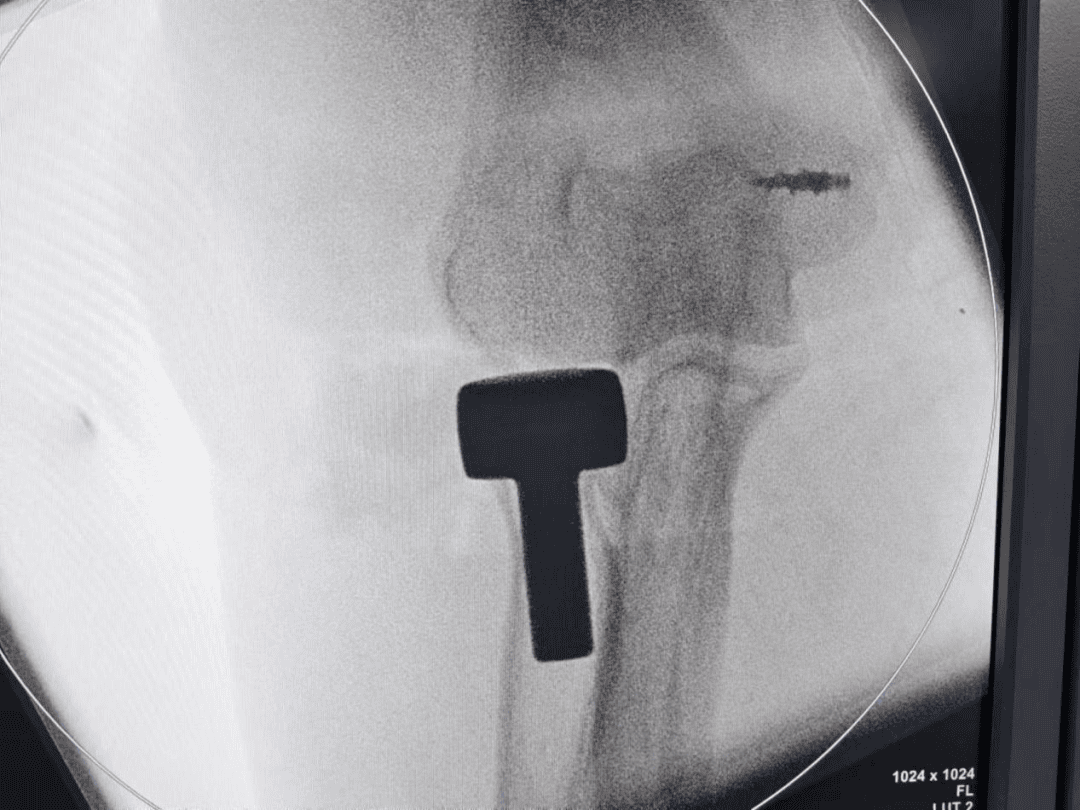

图为患者粉碎的桡骨头

安徽省第二人民医院灵璧医院喻德富副院长、骨科博士、主任医师指导手术。术中探查发现胡女士桡骨头粉碎性骨折,骨碎片游离,尺侧副韧带、环状韧带断裂。骨科手术团队密切协作,按照规范手术治疗方案,小心取出碎骨块,放入假体稳定复位,锚钉重建尺侧受损韧带。术后石膏固定,消肿,预防感染,指导康复锻炼等治疗。